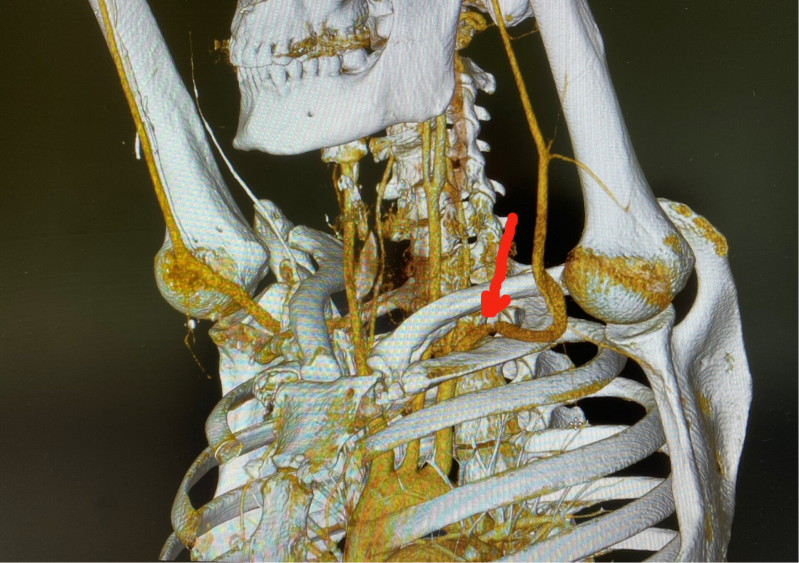

In der Angio-CT Untersuchung in Provokationsstellung, also mit erhobenen Armen, lassen sich nicht nur die Gefässstrukturen sondern insbesondere auch die knöchernen Gegebenheiten rekonstruieren und somit auch subtilere positionsbedingte Irritationen anschaulich in Relation dazu darstellen. In den beiden Beispielbildern lässt sich die Gefässbeteiligung nur durch besondere Blickwinkel ausreichend visualisieren.